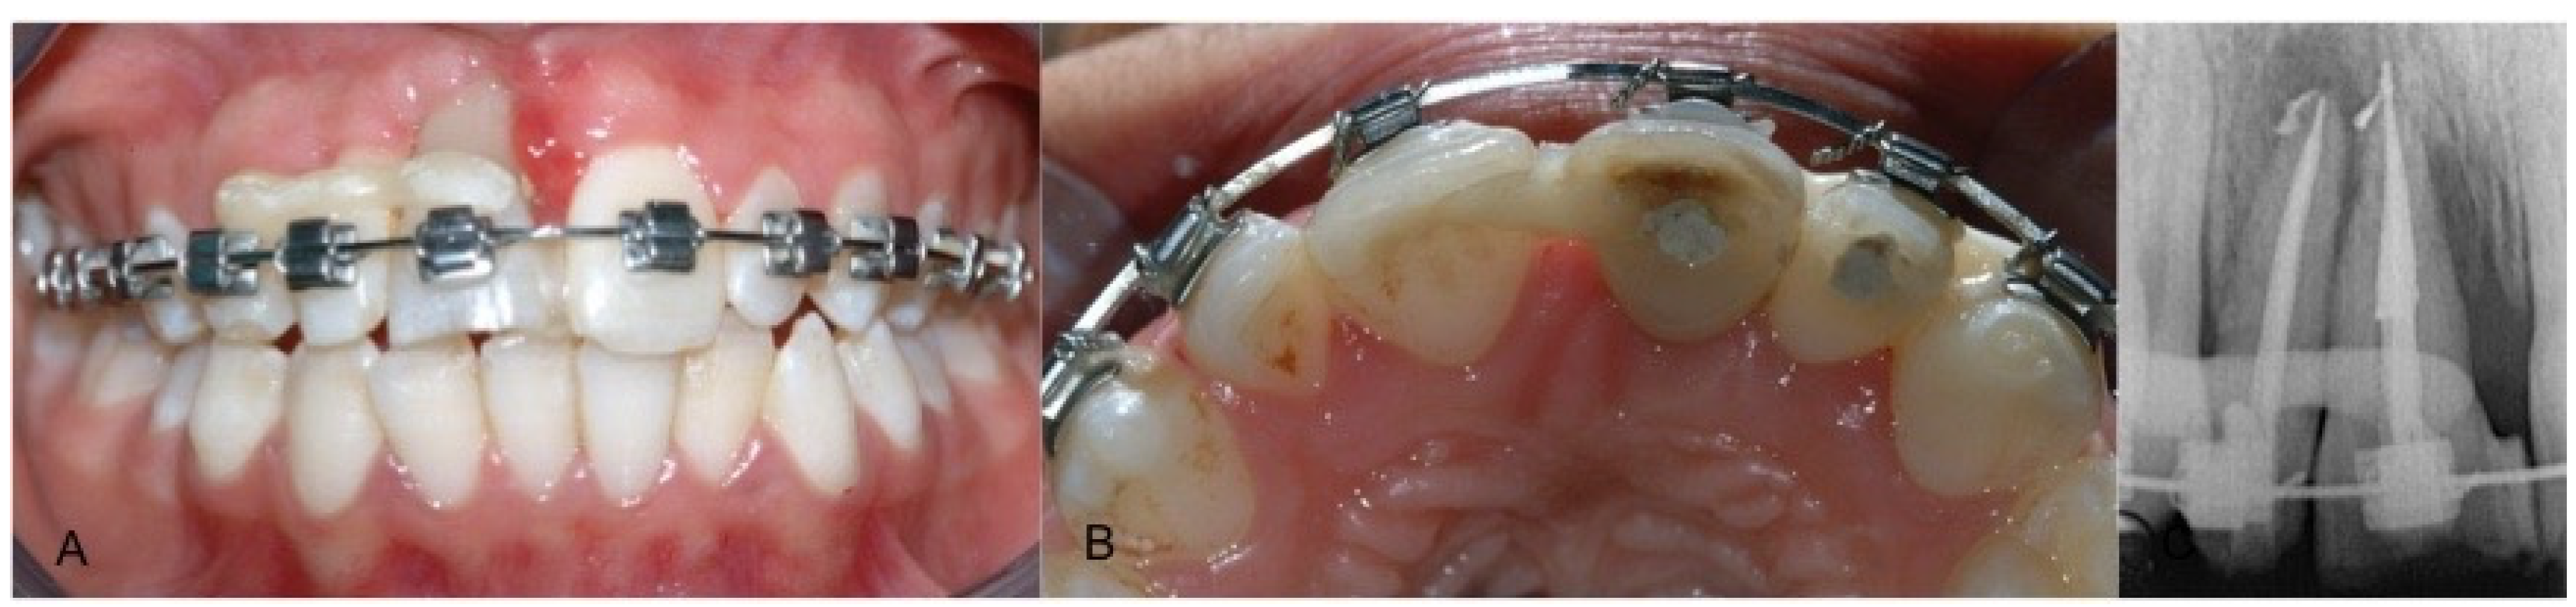

2. Case Report